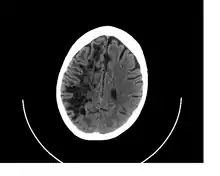

![]() A perivascular space as seen on CT | |

A perivascular space, also known as a Virchow–Robin space, is a fluid-filled space surrounding certain blood vessels in several organs, including the brain,[1] potentially having an immunological function, but more broadly a dispersive role for neural and blood-derived messengers.[2] The brain pia mater is reflected from the surface of the brain onto the surface of blood vessels in the subarachnoid space. In the brain, perivascular cuffs are regions of leukocyte aggregation in the perivascular spaces, usually found in patients with viral encephalitis.

In humans, perivascular spaces surround arteries and veins can usually be seen as areas of dilatation on MRI images. While many normal brains will show a few dilated spaces, an increase in these spaces may correlate with the incidence of several neurodegenerative diseases, making the spaces a topic of research.[4]

Perivascular spaces are distinguished on an MRI by several key features. The spaces appear as distinct round or oval entities with a signal intensity visually equivalent to that of cerebrospinal fluid in the subarachnoid space.[7][14][15] In addition, a perivascular space has no mass effect and is located along the blood vessel around which it forms.[14]